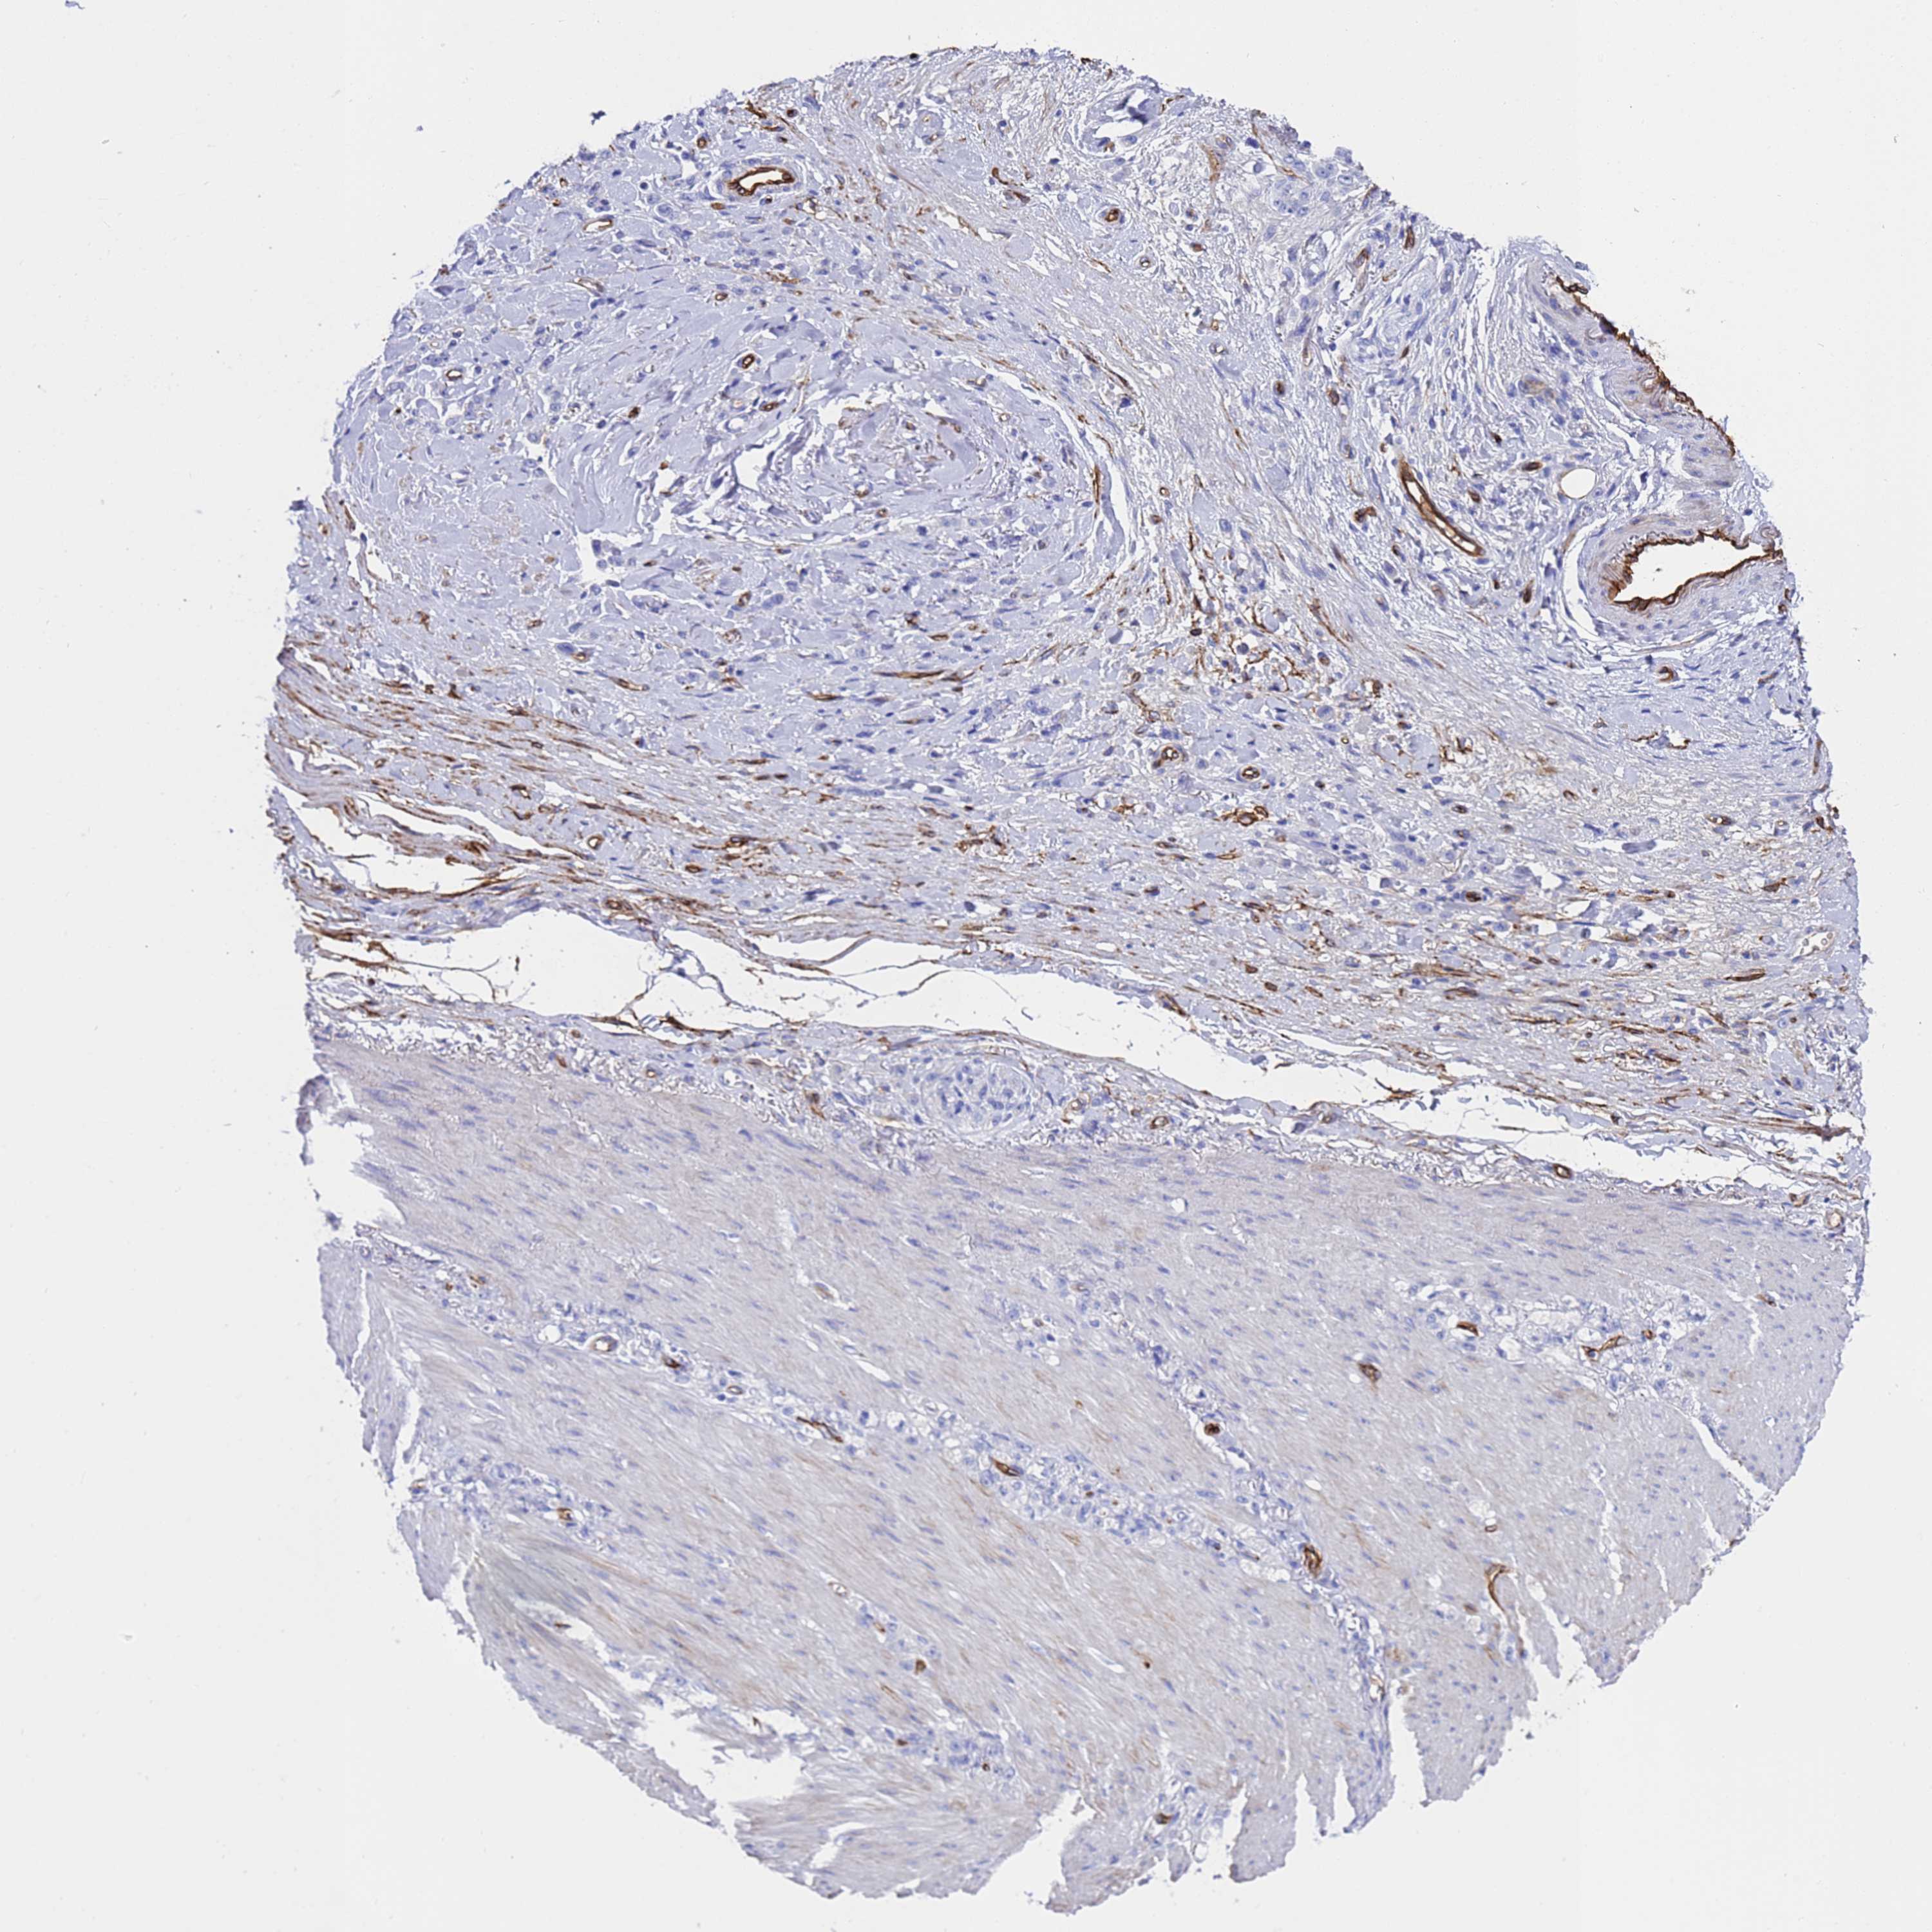

STOMACH CANCER - Protein expressioni

A mouse-over function shows sample information and annotation data. Click on an image to view it in a full screen mode. Samples can be filtered based on level of antibody staining by selecting one or several of the following categories: high, medium, low and not detected. The assay and annotation is described here.

Note that samples used for immunohistochemistry by the Human Protein Atlas do not correspond to samples in the TCGA dataset.

Antibody stainingi

Antibody staining in the annotated cell types in the current human tissue is reported as not detected, low, medium, or high, based on conventional immunohistochemistry profiling in selected tissues. This score is based on the combination of the staining intensity and fraction of stained cells.

Each image is clickable and will lead to virtual microscopy that enables deeper exploration of all samples and also displays staining intensity scores, fraction scores and subcellular localization as well as patient and tissue information for each sample.

Antibody HPA051767

Antibody CAB046467

Staining

High

Medium

Low

Not detected

Intensity

Strong

Moderate

Weak

Negative

Quantity

>75%

75%-25%

<25%

None

Location

Nuclear

Cytoplasmic/membranous

Cytoplasmic/membranous,nuclear

Adenocarcinoma, NOS